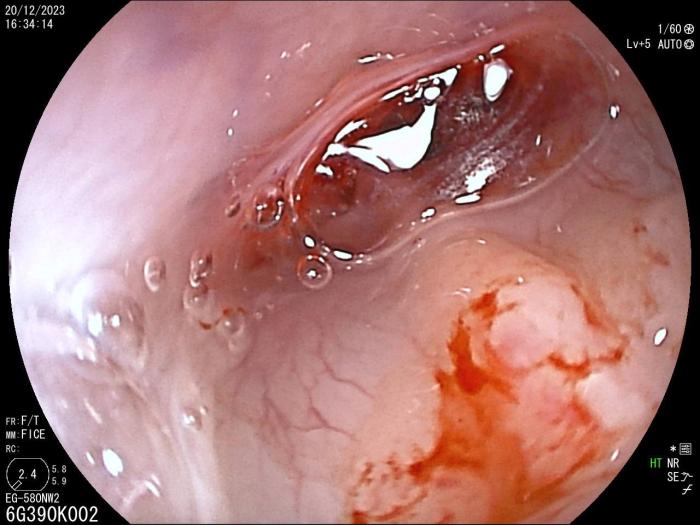

Rinoscopia anterógrada y retrógrada (día 25): se realiza ante la persistencia de secreción nasal bilateral tras antibioterapia, observándose eritema y secreción mucopurulenta y la presencia de un pólipo nasal en la cavidad nasal izquierda (Figura 5A-B), cuyo estudio histopatológico revela una lesión de tipo inflamatorio linfoplasmocitario. La fístula oronasal se ha resuelto completamente. Se observan lesiones líticas en cornetes nasales y endoturbinados.

Al realizar esta técnica, debido a las lesiones y a la dificultad intrínseca del acceso por las características anatómicas, se produce sangrado, siendo necesarios lavados repetidos. Se obtuvo muestra para estudio microbiológico, que en este momento fue recusado por el tutor.